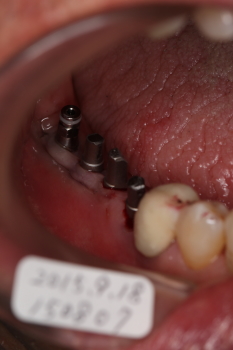

4本のインプラント植立後

一番奥がエミネオ(2回法)インプラント